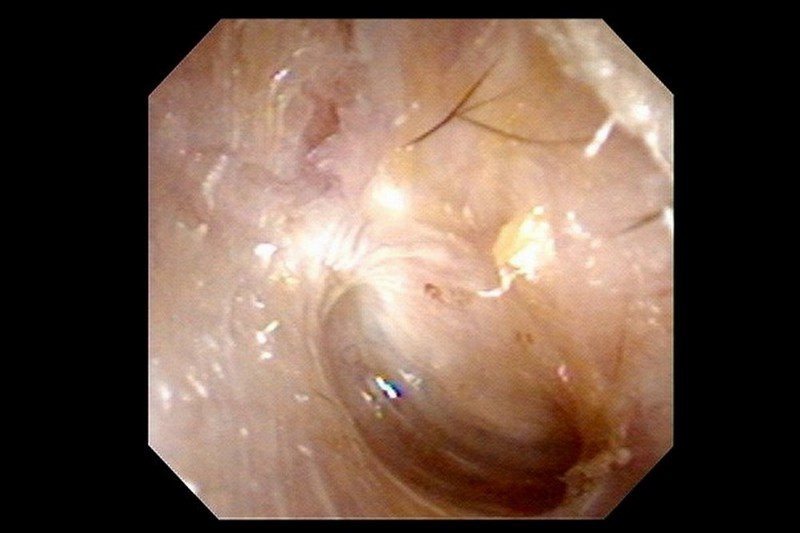

根據《三立新聞網》、《ETtoday新聞雲》報導,台北慈濟醫院耳鼻喉科主治醫師鄭靜雯說明,張先生有慢性中耳炎病史,檢查時發現耳道內都是膿液和皮屑,清理用藥後不僅沒緩解,右臉還「顏面神經麻痺」癱瘓。經過顳骨電腦斷層,張先生確診為「慢性中耳炎併發膽脂瘤」。雖然膽脂瘤是良性的,但已經侵蝕到顱底骨質,導致神經壓迫、右臉面癱。

鄭靜雯醫師說明,扁平上皮細胞長期累積角質,在耳朵裡堆積成膽脂瘤,在中耳或乳突部位較常見。後天的膽脂瘤多和慢性中耳炎相關,耳朵長期發炎、鼓膜穿孔,逐漸在中耳腔形成膽脂瘤,持續侵蝕骨質、破壞聽小骨。張先生住院後先是控制發炎感染,穩定發炎後才手術清除病灶、修補重建鼓室組織,所幸術後恢復良好。